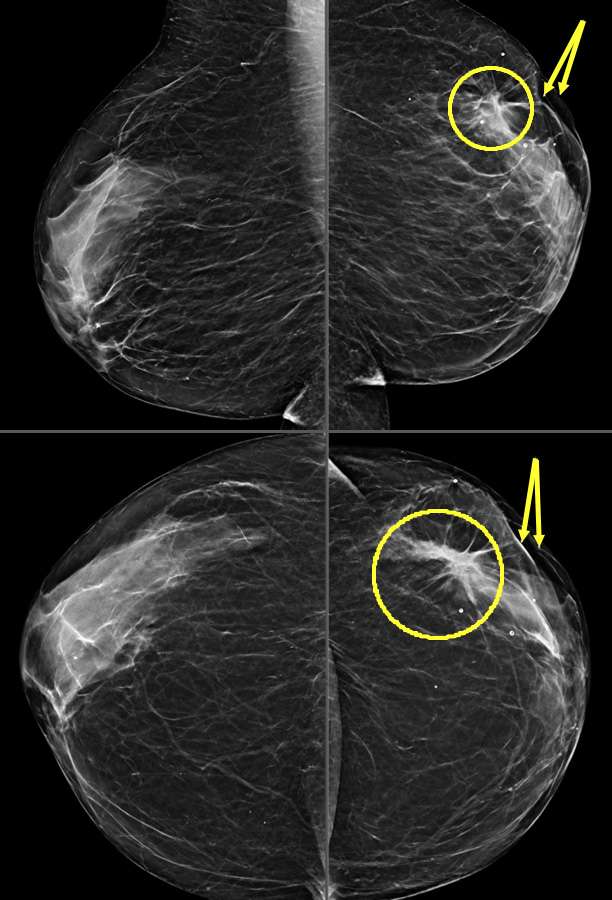

- Mammography: Skin retraction may be noted as an irregular, pulled appearance of the skin. An underlying mass may or may not be mammographically visible.

- Ultrasound: May further reveal distortion in the skin layers but is most helpful in further evaluating the presence of an underlying mass causing the retraction.